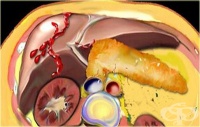

S36.0 Травма на далака

Руптурите на слезката са потенциално живото застрашаващо състояние, настъпващо най-често след коремн...

S36.1 Травма на черния дроб или на жлъчния мехур

Черният дроб като паренхнмен - орган е един от най-често засегнатите в корема органи при травми. Бър...

S36.2 Травма на панкреаса

Нараняванията на панкреаса са сравнително редки поради дълбокото му анатомично разположение в ретроп...